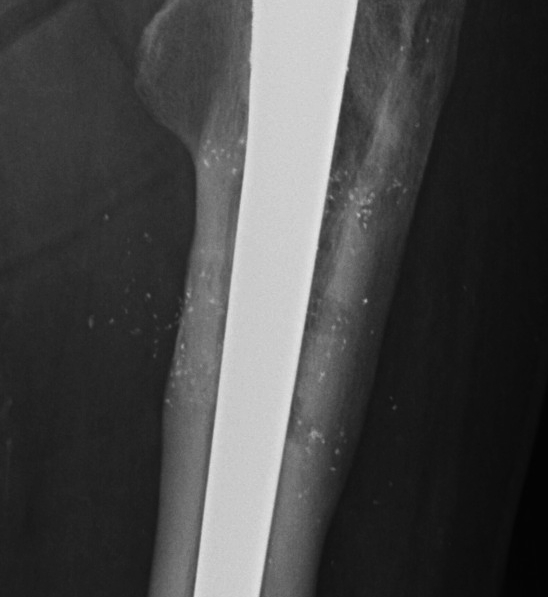

Uncemented femur

Engh classification

Types based on presence of radiolucent lines (RLL)

III Unstable fibrous ingrowth

A.  Component migration

B.  Progressive increase RLL

- divergent RLL

C.  Pedestal formation (bony hypertrophy at tip)

THR Uncemented Subsidence